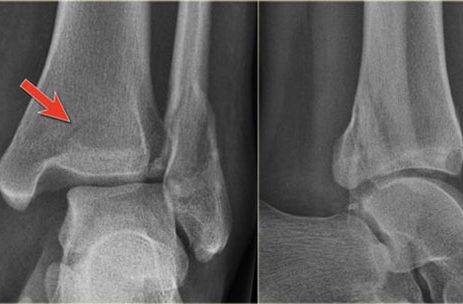

Ankle Fracture

An Ankle Fracture happens when the ankle bones crack or break after receiving a direct impact or being bent too far. The severity of Ankle Fractures fluxuate depending on several factors including: how many bones are broken and if any ligaments are involved. WHAT CAUSES AN ANKLE FRACTURE? Ankle Fractures happen when the bones are severely jarred, or twisted beyond their capability. The stress from this motion causes the ankle to fracture or break. Ankle fractures can be caused by tripping, slipping on an icy surface, missing a step over uneven ground, suddenly twisting your ankle, or blunt force trauma impacting against...